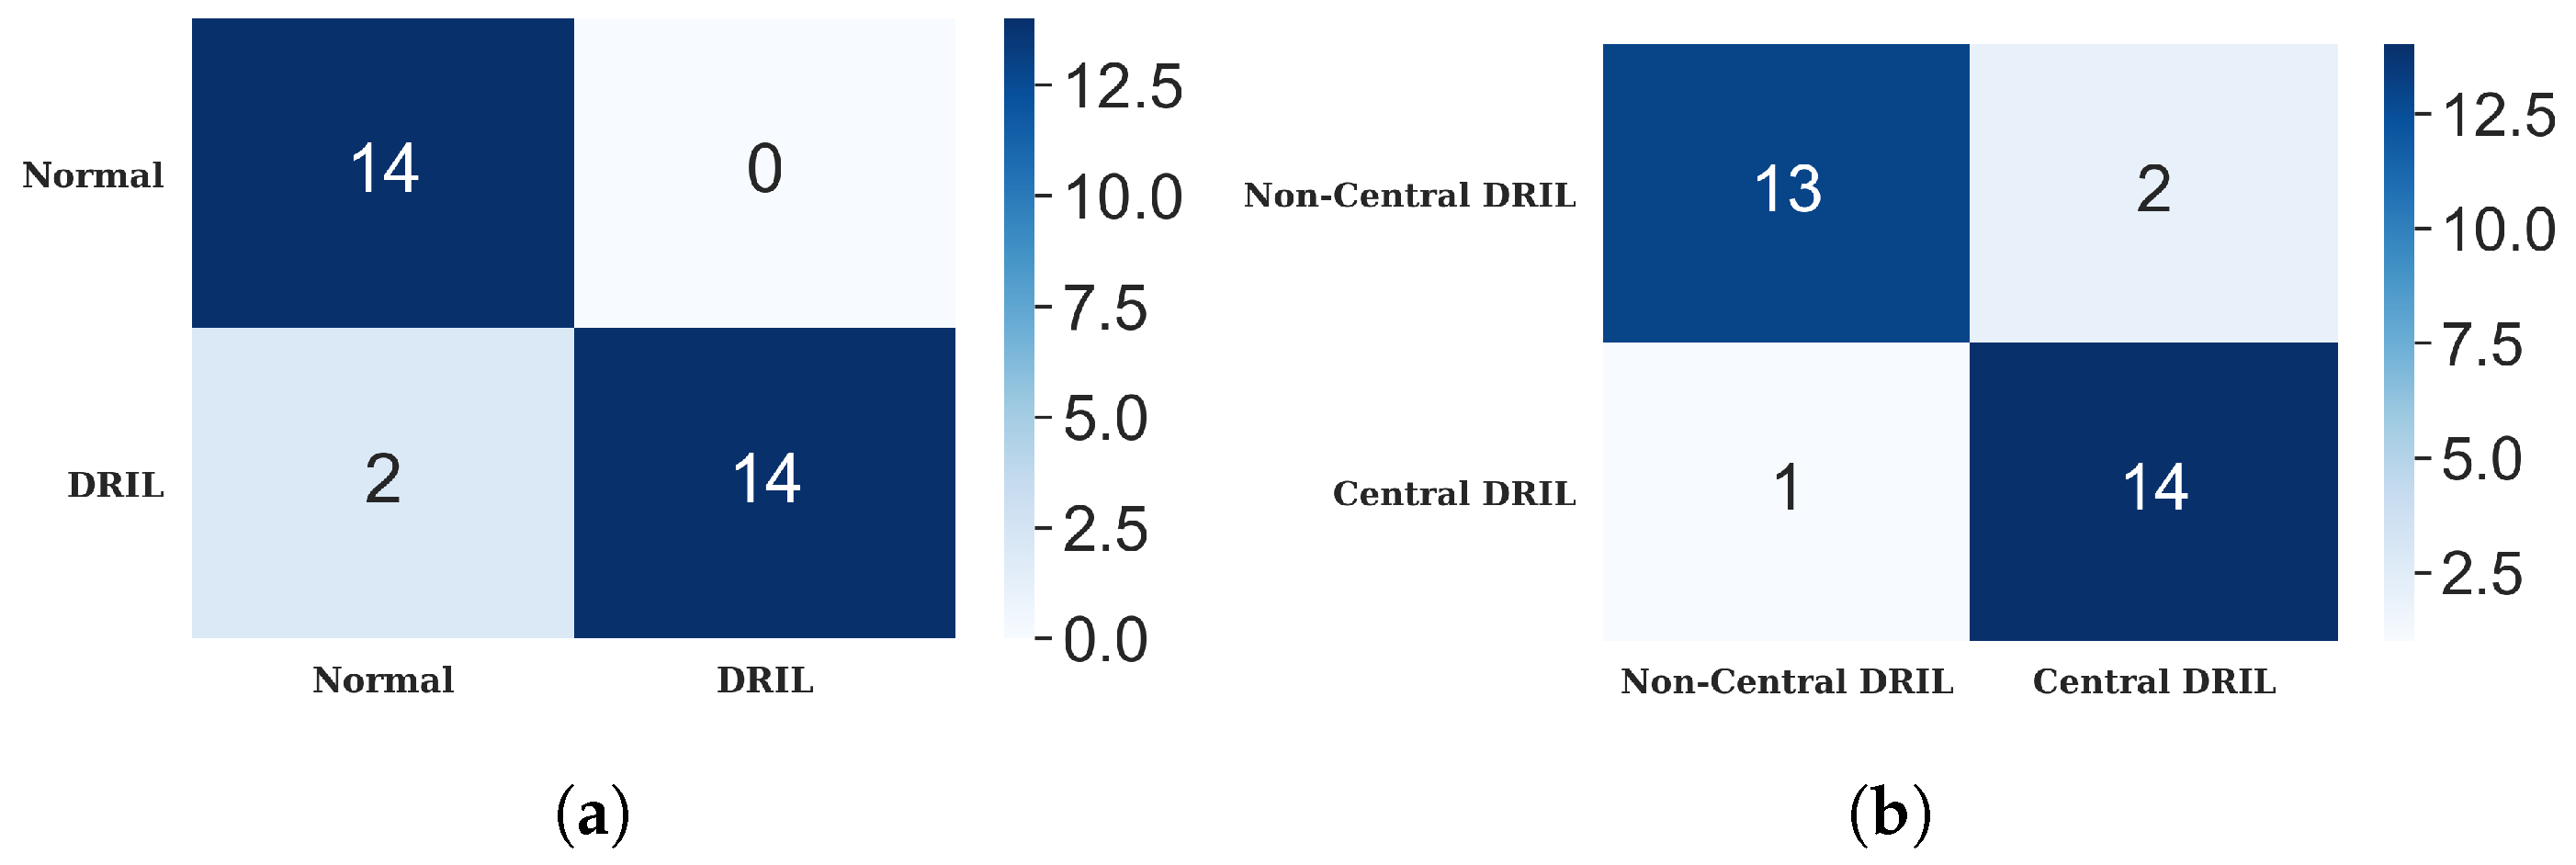

4.3.1. DRIL

| 1 | DRIL/Normal | 100 | 30 | 93.33 | 0.875 | 1.0 | 0.93333 |

| 2 | Central/non-Central DRIL | 100 | 30 | 90.00 | 0.9333 | 0.8666 | 0.9032 |